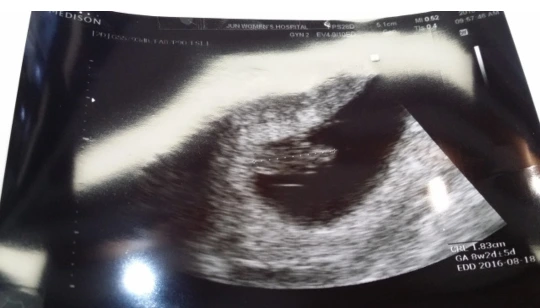

com.daumkakao.android.brunchapp_20190517233312_1_crop.jpeg 초음파 사진으로 보이는 아이가 처음에는 믿기지 않았었다

매번 검진일 때마다 아이의 손가락과 발가락 수를 세심하게 확인시켜주시는 의사 선생님의 노력에도 혹시나 아이에게 내가 모르는 장애가 있을까 봐 걱정하고 또 걱정했었다.